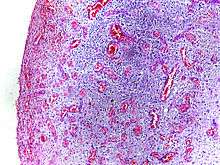

Morphologic patterns

Specific patterns of acute and chronic inflammation are seen during particular situations that arise in the body, such as when inflammation occurs on an epithelial surface, or pyogenic bacteria are involved.

- Purulent inflammation: Inflammation resulting in large amount of pus, which consists of neutrophils, dead cells, and fluid. Infection by pyogenic bacteria such as staphylococci is characteristic of this kind of inflammation. Large, localised collections of pus enclosed by surrounding tissues are called abscesses.